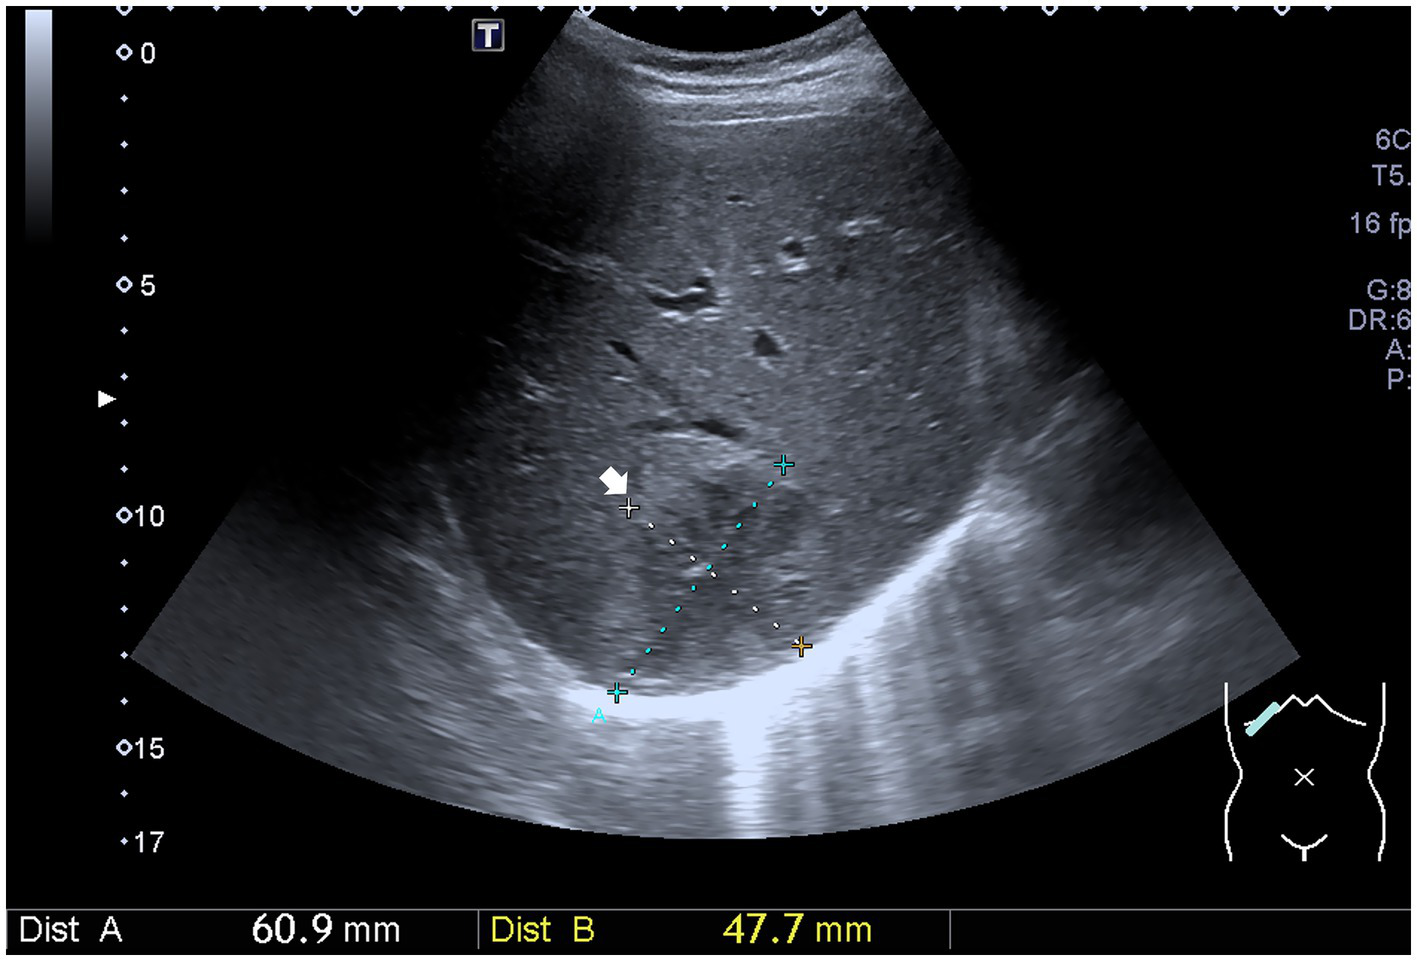

An abdominal sonogram performed on the seventh day of antibiotic treatment and 7 days after PCD revealed a decreasing size of the liver abscess to 6.1 cm x 4.8 cm (Figure 2). During detailed history taking, the patient disclosed engaging in high-risk sexual behavior. Infection was suspected to occur via special contact; hence, hepatitis B virus (HBV) and syphilis tests were checked, and both revealed positive results. No significant symptoms and signs of syphilis were noted, though. Penicillin-G (2.4 million units in a single dose) was then prescribed intramuscularly for syphilis on the 12th day of admission. The patient was discharged in stable clinical condition. Paromomycin (1,500 mg per day orally) was prescribed in the outpatient department. The drainage tube was removed 2 weeks after discharge due to minimal drainage output, and the patient recovered well. The clinical course is documented in Figure 3.

Figure 2

Ultrasound image shows a decreasing size of the liver abscess (white arrow).